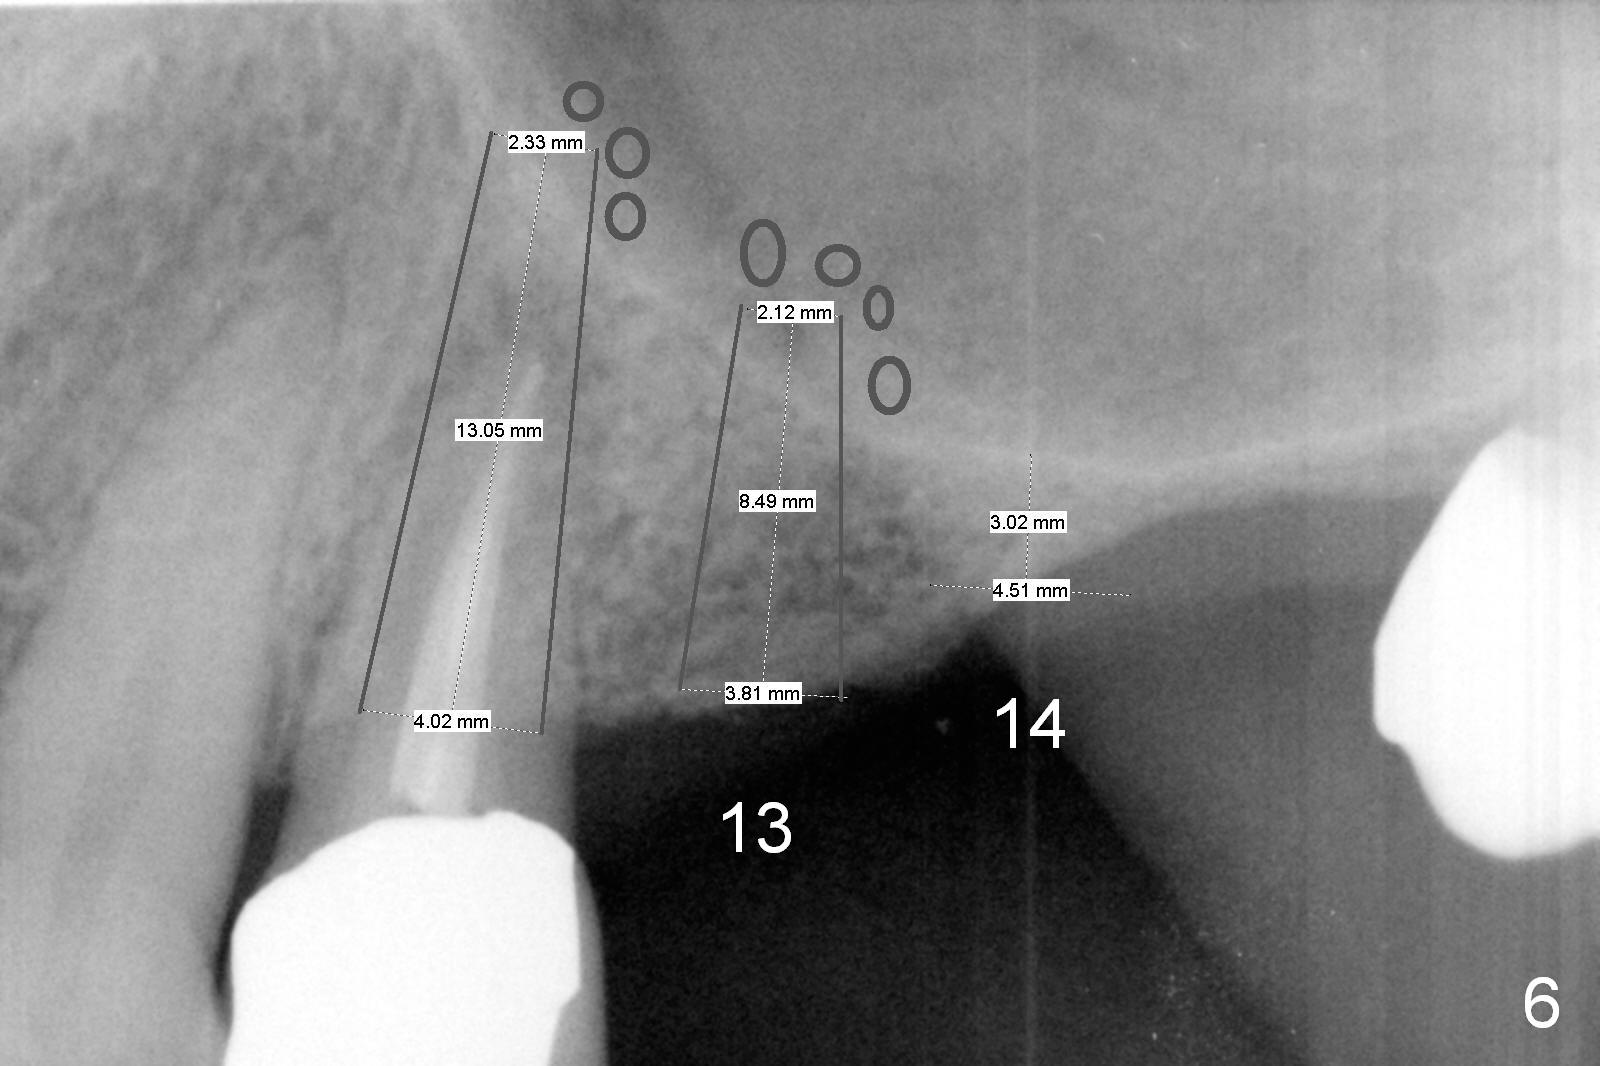

A 64-year-old man (MM) had caries at the tooth #12 (Fig.1), requiring root canal therapy (RCT, Fig.2). One year later, the periapical radiolucency reduces (Fig.3 <, as compared to that in Fig.2). The tooth remains asymptomatic 7 years posts RCT (Fig.4). A year later, the tooth has pain and buccal gingival swelling (probing tenderness); periradicular radiolucency is evident (Fig.5 arrowheads). It appears that the root fractures. Between the 7th and 8th years post RCT, the patient masticated mainly on the left side, while implants were placed at #30 and 31. The patient plans to have 4 implants in the upper left sextant (Fig.6). While implants are being placed at the site of #12 (Clindamycin) and 13, sinus lift seems mandatory at the sites of #13 and (initial depth will be 5-6 mm). By the time implants to be placed at #14 and #15, the bone height may increase.